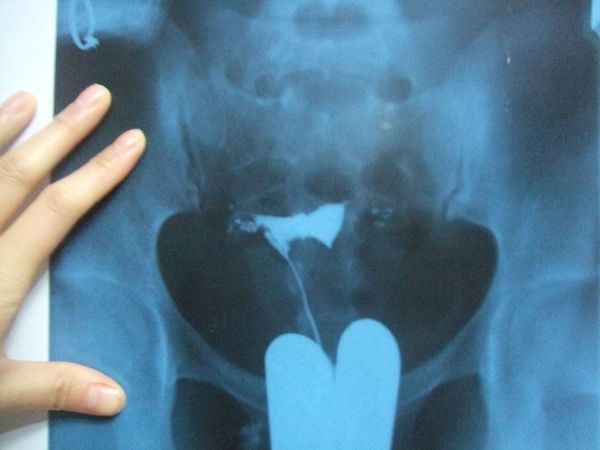

我做之前有查过很多资料,有些是说先打进去,隔天检查,有的说是打进去20分再检查,这一点可能碘油和碘水?有区别,我用的是隔20分就可以检查的那种(不是自己选择的,是医生开药就这样的)

医生用碘酒(黄黄的)涂*体下**和肚子,然后把药水注射进去(这个药水就是造影时医生开的药水,一小瓶)。

然后就可以起来了,起来后等待20分钟,20分钟后再次进去,这时候不需要脱*裤底**,直接有个类似做胸透的机器在小腹上,可能是拍片看碘油/碘水的扩散情况,这个过程很短暂,就结束了,造影到此完成。